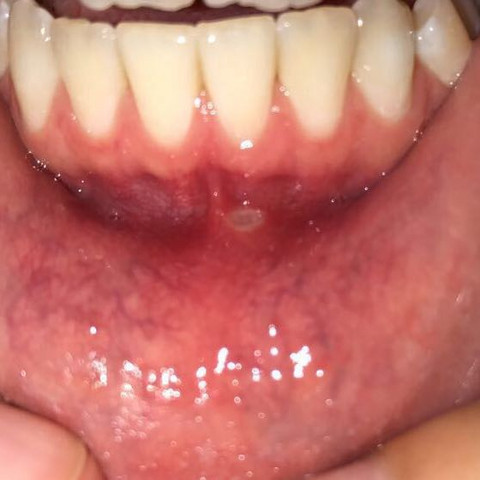

Was tun bei bläschen im mund. Sie sollten aber dennoch beim Arzt oder Zahnarzt abgeklärt werden um ernsthafte Folgen ausschließen zu können. Um das Wachstum der Bakterien zu bekämpfen sollten die Zähne 2 Mal am Tag mit einer weichen Zahnbürste geputzt werden. Damit lassen sich Entzündungen und Schmerzen im Mund abschwächen.

Beim Aufplatzen entsteht eine Wunde die schmerzen und sich entzünden kann. Bläschen im Mund behandeln. Eine gute Mundpflege sollte auch bei Entzündungen im Mund immer beibehalten werden auch wenn es schmerzhaft ist.

Was tun bei Bläschen im Mund Kind. Sind Herpesviren für die Bläschen verantwortlich können antivirale oder schmerzlindernde Medikamente eingesetzt werden. In vielen Fällen verschwinden Blasen im Mund von alleine wieder.

Aphthen und Bläschen im Mund sind zwar äußerst unangenehm aber in 90 Prozent aller Fälle kein Grund zur Sorge. Das hilft bei Aphthen. Es wirkt antiseptisch und bekämpft Bakterien die sich in der Nähe der Aphten befinden.

Damit keine Blasen im Mund entstehen ist die richtige Pflege wichtig. Wie lange dauert Mundfäule bei Kleinkind. Daher geht es bei der Behandlung vor allem darum die Symptome mittels schmerzstillender und entzündungshemmender Mittel Salben Sprays Mundspülungen Medikamente zu lindern.

Wenn die Bläschen im Mund sehr klein sind helfen auch manchmal Eiswürfel die Sie zwischendurch lutschen können. Bläschen auf der Zunge Ursachen und Gegenmaßnahmen Das bekannteste Hausmittel.

Meist reichen aber folgende Maßnahmen für die Behandlung von Aphten im Mundbereich und der Intimregion. Bläschen im Mund behandeln. Die Therapie der fiesen Bläschen im Mund zielt auf eine Symptomlinderung. Zudem können schmerzlindernde und fiebersenkende Mittel hilfreich sein etwa Zäpfchen oder Saft mit Ibuprofen oder Paracetamol. Auch das Teebaumöl aus der Apotheke ist gut zur Desinfektion und Schmerzstillung. Denn die Ätiologie einer Aphthosis ist ungeklärt auch wenn es Faktoren gibt seien es Erkrankungen Nahrungsmittel. Bläschen im Mund. Beim Major-Typ kann der Heilungsprozess länger dauern. Damit lassen sich Entzündungen und Schmerzen im Mund abschwächen.

Handelt es sich tatsächlich um eine Aphte wird der Arzt in schweren Fällen zu Kortison raten. Lidocain oder desinfizierend zB. Mindestens zweimal am Tag. Ob im Mund oder an den Genitalien. Sind Herpesviren für die Bläschen verantwortlich können antivirale oder schmerzlindernde Medikamente eingesetzt werden. Spülungen mit Gurgellösungen die desinfizierend antiseptisch wirken. Daher geht es bei der Behandlung vor allem darum die Symptome mittels schmerzstillender und entzündungshemmender Mittel Salben Sprays Mundspülungen Medikamente zu lindern.